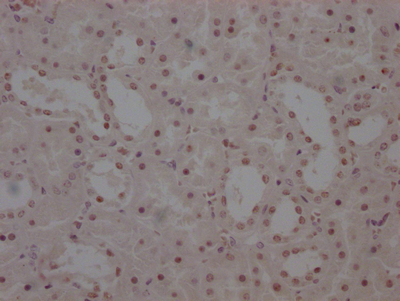

The image on the left is immunohistochemistry of paraffin-embedded Human brain tissue using CSB-PA297945(KRT13 Antibody) at dilution 1/35, on the right is treated with fusion protein. (Original magnification: ×200)